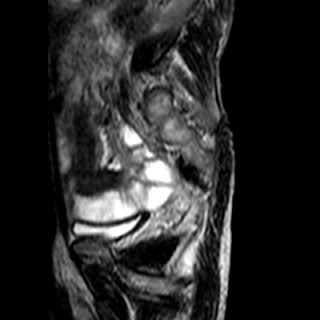

Radiological images (MRI):